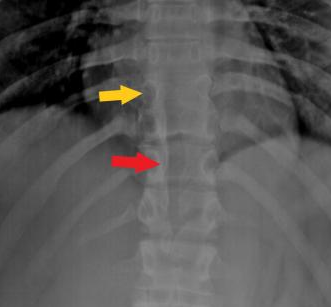

The spinal cord is abnormally divided in the sagittal plane, resulting in this condition (hemicords). Diastematomyelia often coexists with various spinal dysraphisms, including meningocele, spinal lipoma, myelomeningocele, neurenteric cysts or dermal sinuses, and vertebral anomalies, including hemivertebrae, butterfly vertebrae, or scoliosis.

In diastematomyelia, the cord is split in a direction that is either sagittal or longitudinal. The “splitting” mostly occurs entirely among the “hemicords” or only partially. The hemicord splits in the center, and the two halves then come together in the lower portion of the cord.

Since the cause of the issue’s growth is uncertain, it is referred to as a “dysraphic state.” Typically, diastematomyelia affects the spine between the ninth thoracic and first sacral segments. Most sacral pain originates from the lumbar spine, which is located higher up. The condition occurs seldom in the cervical region.